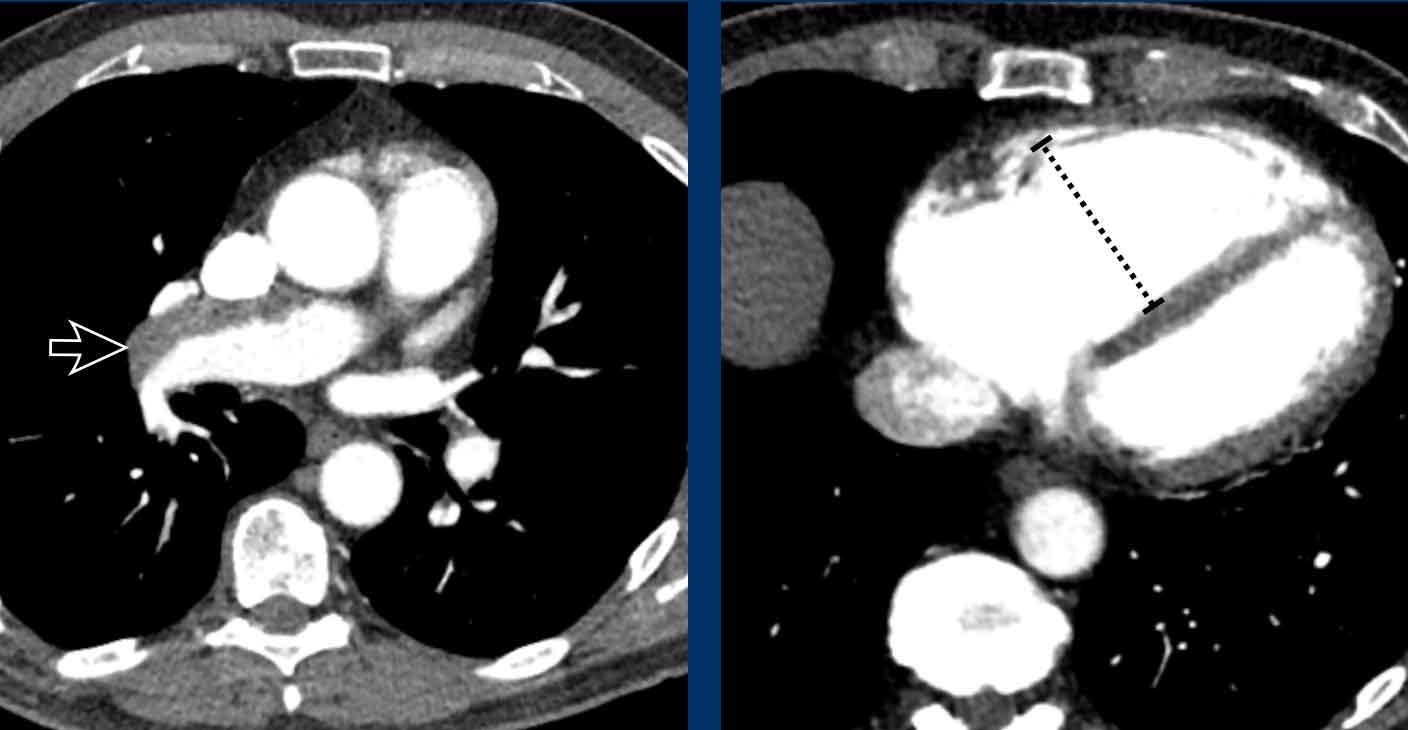

Hình ảnh

Tình cờ phát hiện tâm thất trái giãn nặng.

Đường kính ngang của tâm thất trái > 70 mm.

Phì đại tâm thất trái đồng tâm trong tăng huyết áp mạn tính với độ dày lên đến 26 mm tại vách liên thất đoạn nền.

Đây là bất thường ngay cả trong thì tâm thu.